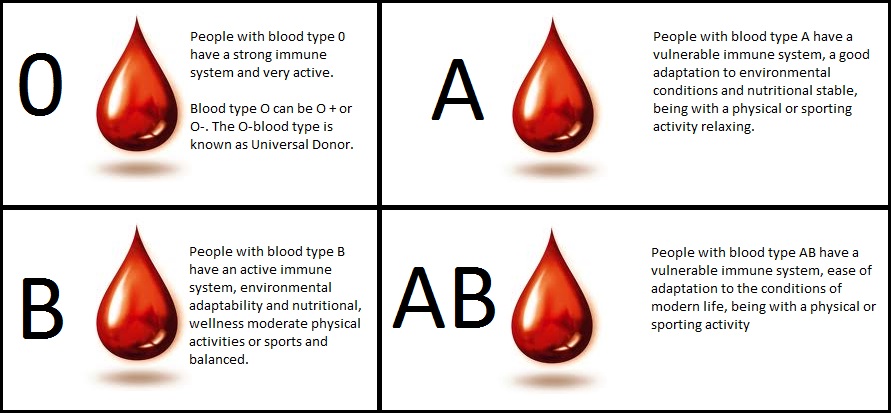

- Components of blood and their functions (Red blood cell, white blood cell, platelets and plasma (blood groups)

- Importance of blood tests & blood groupings e.g. HIV/AIDS cell anemia